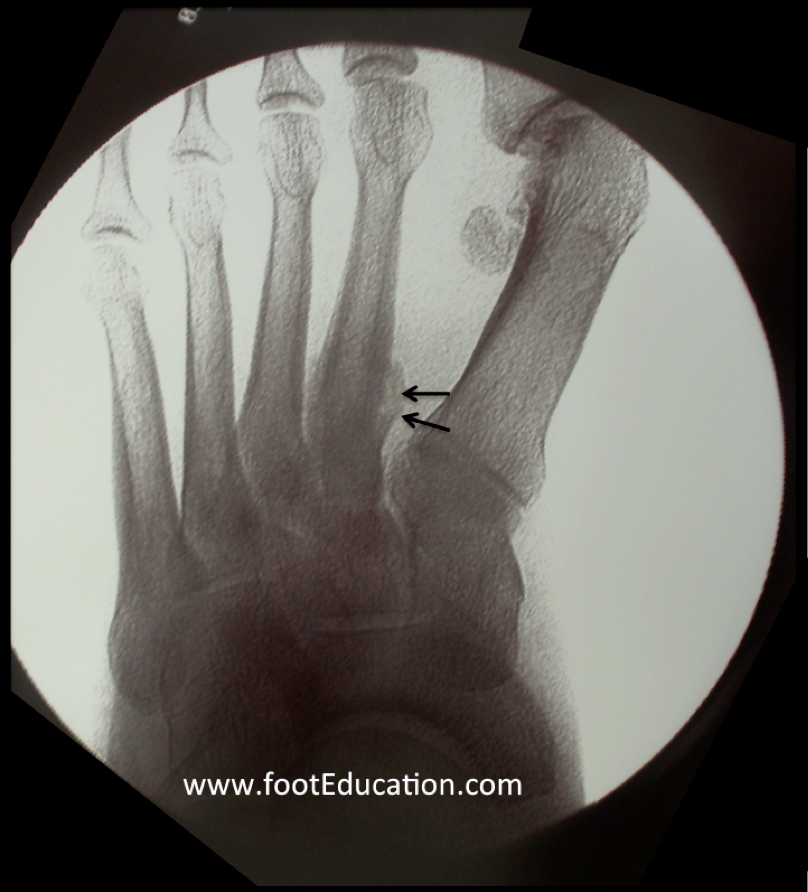

Repeated Metatarsal Stress Fractures. This is different from an acute fracture, which is when you break a bone suddenly due to an accident, fall, or collision. Web a stress fracture is a small crack in a bone, or severe bruising within a bone. Web metatarsal fractures may result either from direct or indirect violence, and they display a wide variety of injuries ranging from isolated, simple fractures of one. Web a metatarsal stress fracture is a fracture to one of the metatarsal bones—the long bones in the foot that connect your heel and arch to your toes—and occurs due to repeated stress or injury. Web stress fractures are exactly what their name sounds like — fractures that happen when something puts too much stress on your bone. This may be due to sudden injury. Web stress fractures are small incomplete fractures that often involve the metatarsal shafts. Web a metatarsal fracture occurs when one of the long bones of the midfoot is cracked or broken. Most stress fractures are caused by overuse and. Web the other variety of fractures that are commonly seen in metatarsal bones is stress fractures which result from a small amount of repetitive force and are.

This may be due to sudden injury. Most stress fractures are caused by overuse and. Web a metatarsal stress fracture is a fracture to one of the metatarsal bones—the long bones in the foot that connect your heel and arch to your toes—and occurs due to repeated stress or injury. This is different from an acute fracture, which is when you break a bone suddenly due to an accident, fall, or collision. Web stress fractures are small incomplete fractures that often involve the metatarsal shafts. Web a metatarsal fracture occurs when one of the long bones of the midfoot is cracked or broken. Web a stress fracture is a small crack in a bone, or severe bruising within a bone. Web stress fractures are exactly what their name sounds like — fractures that happen when something puts too much stress on your bone. Web metatarsal fractures may result either from direct or indirect violence, and they display a wide variety of injuries ranging from isolated, simple fractures of one. Web the other variety of fractures that are commonly seen in metatarsal bones is stress fractures which result from a small amount of repetitive force and are.

Repeated Metatarsal Stress Fractures Web metatarsal fractures may result either from direct or indirect violence, and they display a wide variety of injuries ranging from isolated, simple fractures of one. Web a stress fracture is a small crack in a bone, or severe bruising within a bone. Web a metatarsal stress fracture is a fracture to one of the metatarsal bones—the long bones in the foot that connect your heel and arch to your toes—and occurs due to repeated stress or injury. Web the other variety of fractures that are commonly seen in metatarsal bones is stress fractures which result from a small amount of repetitive force and are. Most stress fractures are caused by overuse and. Web stress fractures are exactly what their name sounds like — fractures that happen when something puts too much stress on your bone. Web metatarsal fractures may result either from direct or indirect violence, and they display a wide variety of injuries ranging from isolated, simple fractures of one. This is different from an acute fracture, which is when you break a bone suddenly due to an accident, fall, or collision. Web a metatarsal fracture occurs when one of the long bones of the midfoot is cracked or broken. This may be due to sudden injury. Web stress fractures are small incomplete fractures that often involve the metatarsal shafts.